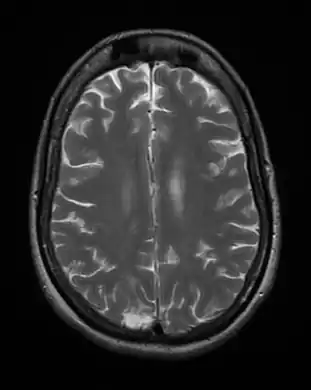

Cerebral toxoplasmosis (with primary involvement in the right occipital lobe)

Cerebral toxoplasmosis